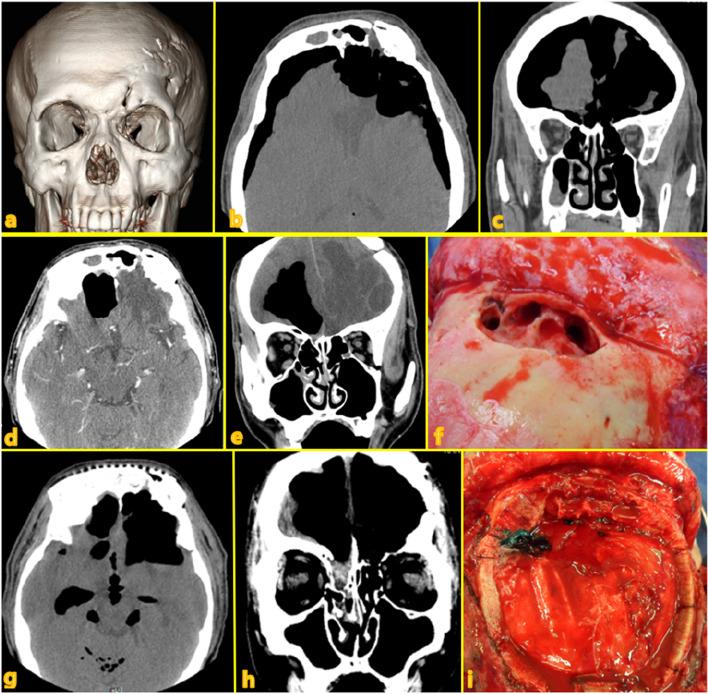

Frontal sinus injuries are relatively rare among facial bone traumas. Without proper treatment, they can lead to fatal intracranial complications, including meningitis or brain abscesses, as well as aesthetic and functional sequelae. The management of frontal sinus injuries remains controversial, with various treatment methods and outcomes being reported. This article describes the clinical characteristics, surgical methods, and outcomes among 17 patients who underwent surgery for frontal sinus injury and related complications.

We retrospectively included 17 patients who underwent surgery for frontal sinus injury and its related complications at the Kangwon National University Hospital between July 2010 and September 2021. Among them, six underwent simple open reduction and fixation of the anterior wall, eight underwent sinus obliteration, and three underwent cranialization. Two patients who underwent sinus obliteration died due to infection-related complications. The patient who underwent cranialization reported experiencing chronic headache and expressed dissatisfaction regarding the esthetic outcomes of the forehead. Except for these three patients, the other patients achieved satisfactory esthetic and functional recovery.